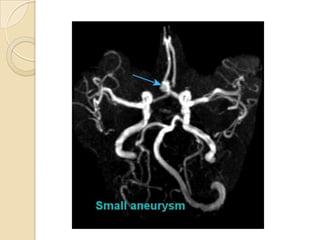

 3D TOF is now accepted as a non-invasive screening tool for

familial aneurysmal disease.

 Sensitivity is greater for detecting aneurysms > 3mm (94%)

than aneurysms < 3mm (38%). ( White et al 2000)

 Overall inferior to DSA and misses aneurysm <3mm.(Adams

et al 2000)